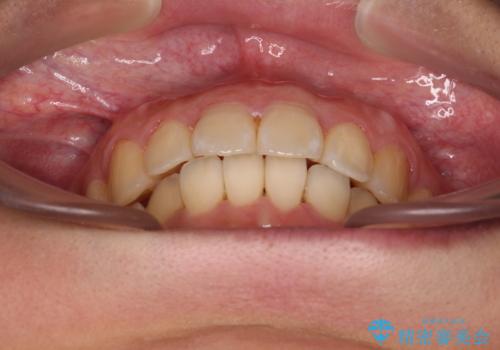

前に出ている前歯を引っ込めたい インビザライン矯正

- 前方に傾斜した上下の前歯を気にして来院された患者様です。

唇の閉じにくさや横顔のシルエットが気になるような突出感ではなかったため、インビザラインを用いて、歯列の遠心移動とIPR(歯と歯の間を削る)により前歯の傾斜を改善していくこととしました。